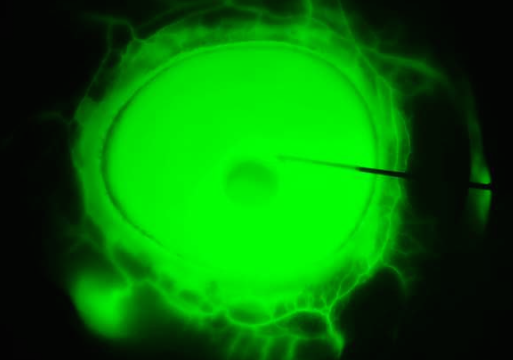

• Multiscale analysis of equatorial sclera anisotropy: Revealing discrepancies in fiber orientation and mechanical properties

• Li R, Hua Y, Zhang F, Qian X, Gong C, Wan X, Waxman S, Zeng Y, Che Z, Zhang J, Jin W, Humayun MS, Chen Z, Sigal IA, Zhou Q.

• Science advances, 11(28), eadp8631. https://doi.org/10.1126/sciadv.adp8631